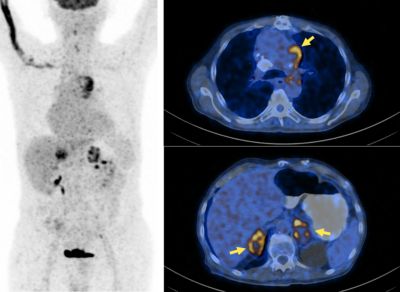

64 Cu Dotatoc Pet Ct In Patients With Neuroendocrine Tumors Springerlink

64 Cu Dotatoc Pet Ct In Patients With Neuroendocrine Tumors Springerlink from media.springernature.com